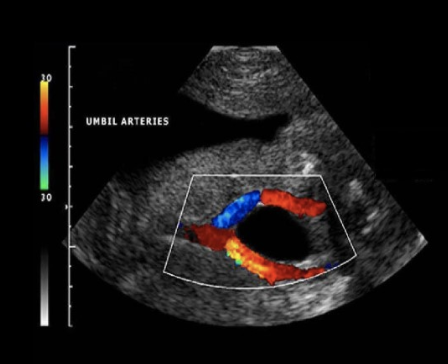

while performing an anatomy scan on a 22w fetus, you are unable to obtain a cross-sectional image of the umbilical cord to show the number of umbilical arteries.

what is an alternative method to evaluate the arterial anatomy of the cord

a) obtain a cross-section view of the umbilical cord insertion at the placenta + apply color doppler

b) obtain a transverse view of the fetal abd at the level of the kidneys + apply color doppler

c) obtain a transverse view of the fetal pelvis at the level of the bladder + apply color doppler

d) obtain a midline sagittal view of the fetus that includes the fetal bladder + apply color doppler